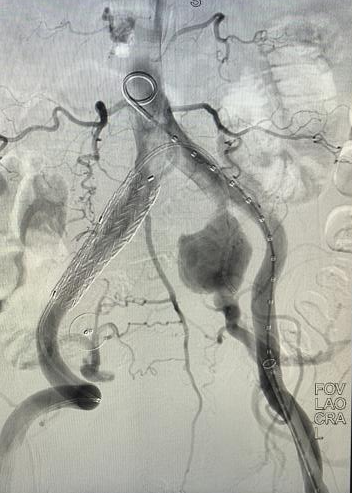

心脏问题解决后,治疗的“接力棒”交到了血管外科团队手中。团队预先在腹主动脉支架上为副肾动脉开窗并标记,随后在术中精准定位,将导丝导管通过开窗口超选入副肾动脉并成功植入支架,最终造影显示,腹主动脉瘤被完全隔绝,副肾动脉血流通畅,且无内漏。术后,患者肾功能维持良好,平安出院。

精准“束径”,为支架锚定与隔绝瘤体打下坚实基础

精细“开窗”,为副肾动脉预留生命的“侧门”